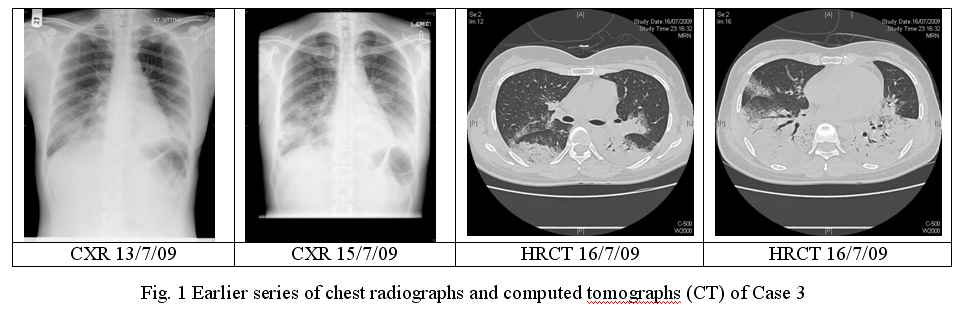

With her persistent high fever, she was transferred to our medical ward on 15/7/09 at around 9 pm. Her SaO2 was only 85% upon the transfer. Intravenous Amoxycillin- Clavulanate was switched to Cefepime empirically but her condition did not improve, and she was transferred to ICU subsequently on 16/7/09. Her SaO2 dropped to 90% while she was on 4 L/min of oxygen. ABG showed type I respiratory failure. Repeated WBC was normal with persistent lymphopenia while the liver and renal function tests were normal. CK and LDH levels were mildly elevated to 261 and 341 IU/L respectively and the first CRP was 202mg/L. Blood for HIV was negative. Repeated CXR showed marked increase of consolidative changes over both lower zones and HRCT confirmed wide spread airspace shadowing over corresponding areas. (Fig.1)